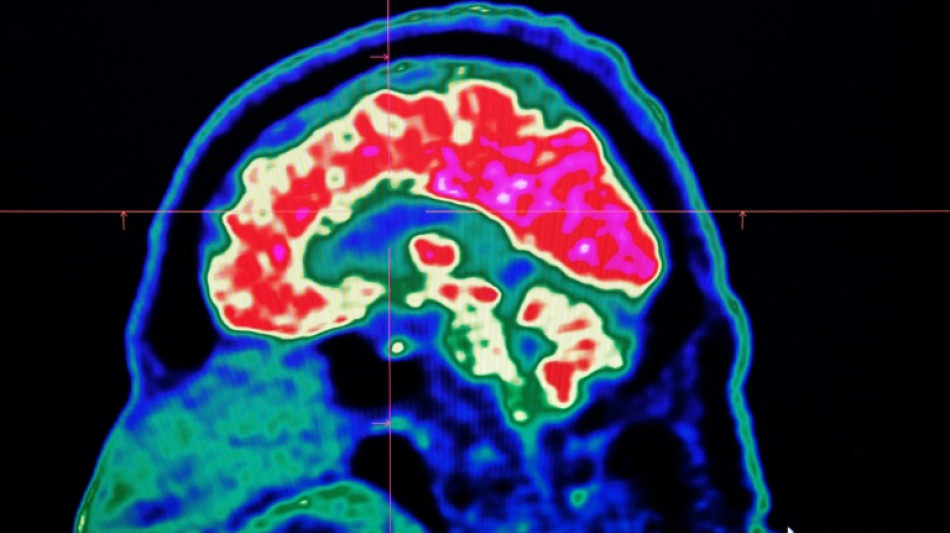

Final report casts doubt on existence of Canada mystery brain illness / Photo: © AFP